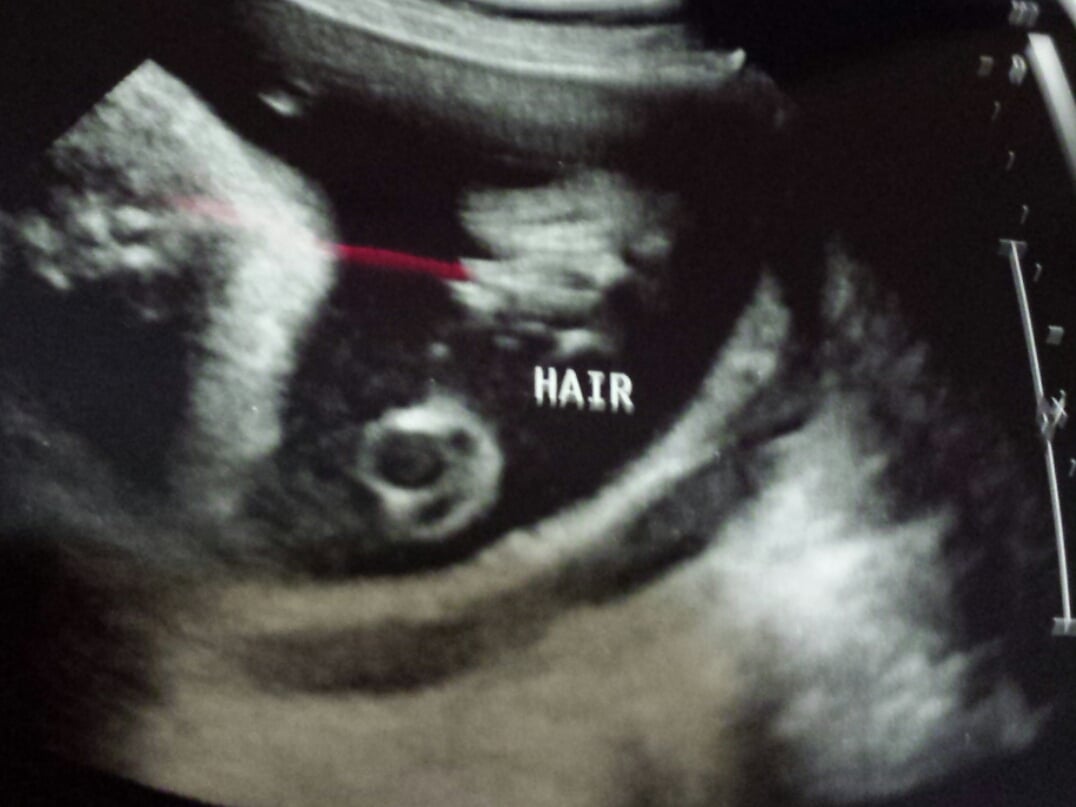

This is our Elijah at 33 weeks. I am trying to decide if that is hair on his head or shadow? I didn't pay enough attention to ask before we left. What do you ladies think?

• No idea. They spotted hair on my 19w ultrasound. It looked like little spikey fuzz coming off the top of the scalp; but it wasn't a 3D us.

• The little white spikes are Ellie's hair ☺️☺️ The specialist said holy she has a lot of hair when, when he was doing the ultrasound